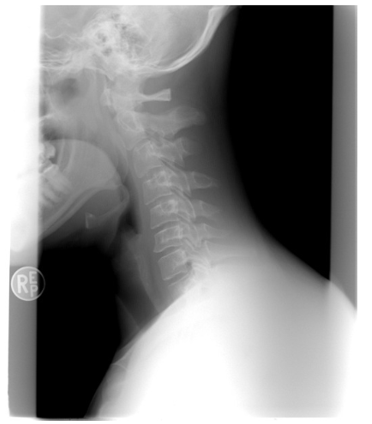

3. 영상 검사: 목 디스크를 확인하기 위해 X-ray, MRI (자기공명영상), CT (컴퓨터 단층 촬영) 등의 영상 검사가 수행될 수 있습니다. 이를 통해 디스크의 위치, 크기, 손상 정도 등을 평가할 수 있습니다.